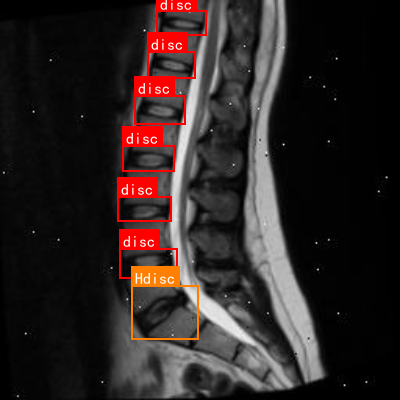

上图展示了一张典型的腰椎MRI矢状位图像,其中标注了正常椎间盘("disc")和异常椎间盘("Hdisc")。通过对比这些标注,我们的模型可以学习到正常与异常椎间盘之间的差异,从而实现准确的检测与分类。

上图展示了腰椎间盘突出的典型影像学表现,可以看到椎间盘向不同方向突出的情况。基于深度学习的模型能够自动识别这些特征,辅助医生进行诊断。